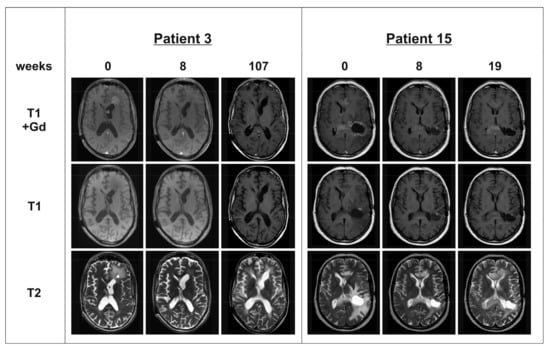

Figure 1. Magnetic resonance imaging (MRI) of patients 3 and 15: T1 sequences with and without Gadolinium (Gd) contrast enhancer and T2 sequences were obtained at baseline, follow-up at 8 weeks after Bevacizumab (BEV) therapy initiation and at relapse. Patient 3 achieved partial response (PR) under BEV therapy combined with irinotecan. At week 107, patient 3 showed a progressive contrast enhancement in the area of the septum pellucidum. Patient 15 reached PR under BEV monotherapy. At week 19, both contrast-enhancing lesions (in the anterior and posterior part of the corpus callosum) progressed.

In the patient group with mfGB, we observed as best response a partial response (PR) in 11 patients, stable disease (SD) in two patients, mixed response (MR) in one patient, and progressive disease (PD) in two patients (see Table 1 and Figure 1). In the sGB matched control cohort, best response was PR in nine patients, SD in three patients, MR response in one patient, and PD in three patients (see Table 2). There was no significant difference in PFS and OS between patients with mfGB and sGB. However, there was a clear trend for shorter OS in mfGB as compared to sGB (see Figure 2). Median PFS was 21 weeks for patients with mfGB, and 23.5 weeks for their matched controls with sGB. Median OS was 33 weeks in the mfGB group, and 43.5 weeks in the sGB group. One patient in each group was still alive at the time of data analysis (patient 3 at week 313 and patient C16 at week 129). In the mfGB group, Karnofsky performance score (KPS) improved after initiating BEV therapy in five patients, stabilized in 10 patients, and deteriorated in one patient. In the matched control group of sGB patients, KPS improved in four patients, stabilized in 10 patients, and deteriorated in two patients. In the mfGB group, steroid intake was reduced after BEV therapy initiation in 13 patients and was left untouched in three patients. In no mfGB patient did the steroid dose have to be increased. In the sGB control cohort, steroid intake was reduced in 12 patients, left unchanged in three patients, and had to be escalated in one patient. To evaluate if the tumors developed an even more infiltrative phenotype under BEV therapy, we explored the share of new lesions (T1 contrast enhancing separated by at least 1 cm from existing lesions) on the last magnetic resonance imaging (MRI) showing progression before the start of BEV therapy and at progression under BEV therapy. In the mfGB goup, new lesions were observed in 40% prior to BEV therapy initiation and in 23.1% of the relapses under BEV therapy (p = 0.36). In the sGB control cohort, new lesions occurred in 31.3% prior to and in 21.4% under BEV therapy (p = 0.56; see Table 3). There was no significant difference in the frequency of new lesions between the mfGB and sGB groups (p = 0.62 prior to BEV therapy; p = 0.92 under BEV therapy).